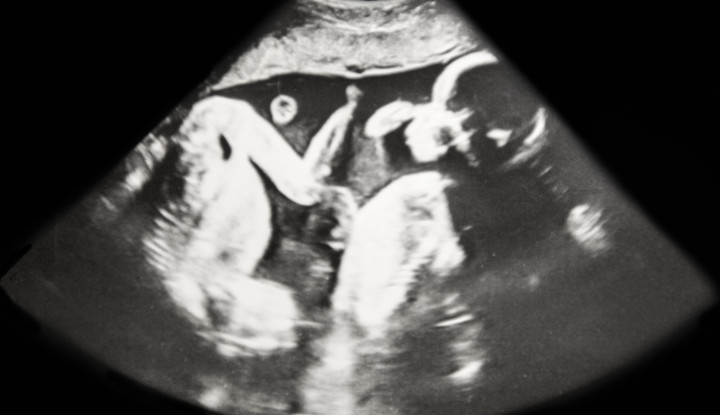

Egy kínai kutatócsoport vezetője, Ho Csienkuj hétfőn bejelentette, hogy nemrégiben megszületett egy ikerpár – Lulu és Nana – akiken sikeresen alkalmazták a legújabb, ún. CRISPR-alapú genomszerkesztést – írja a Qubit.